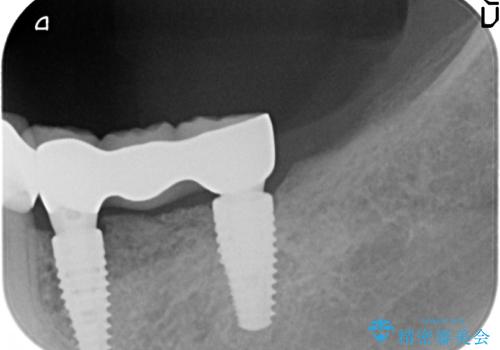

咬合機能を回復し、満足して食事を行えるようインプラント治療を計画します。

- 80万円(インプラント×2・アバットメント×2・ジルコニアクラウン×3)費用は治療当時の料金となります